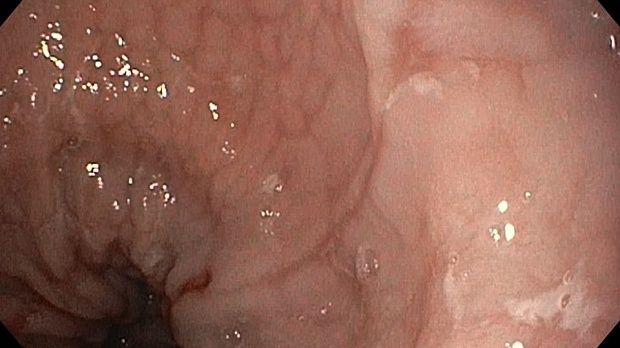

Публикации из социальных сетей: “Cobblestone esophagitis” (эзофагит со слизистой булыжной мостовой)

“Cobblestone esophagitis” (эзофагит со слизистой булыжной мостовой) - редкая эндоскопическая находка и ассоциируется с эозинофильным эзофагитом, кандидозом и пищеводом Барретта у взрослых. Он также может быть найден при тяжелом рефлюкс-эзофагите, вторичен к дистальной обструкции гастроинтестинального тракта. В нашем случае - это пациент после с 9-летним стажем бандажирования кардиального отдела желудка, признаками дуоденостаза, фундальной эрозивной гастропатией, расширением пищевода и уровнем жидкости в нем при горизонтальном положении, грыжи ПОД, эрозивно-язвенном дистальном эзофагите.. Пациент просто пришел удалить полип в прямой кишке и заодно посмотреть, что творится в желудке.... Ацетообеление+NBI+биопсия. ИПП на 3-4 мес и повтор для решения о Барретте.